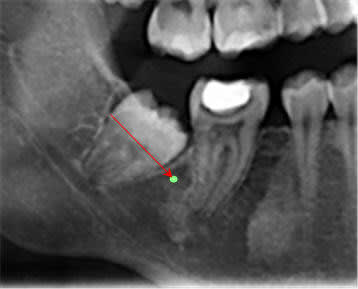

Un orthodontiste me refère une patiente avec le même problème au niveau des dernières molaires (patientes 12 ans) aux ma=xillaires inférieures; il me demande d'exposer les dents. Comment le faite-vous? en profitez-vous pour faire un peu d'ostéoplastie en distal? Dans mon cas l'arcade de 6 à 6 est en place.La distalisation des 6 a empêché l'éruption des 7.

Il ne faut pas rêver, quand on voit la radio, on imagine la faible amplitude de mouvement qu’un tel système apporterait… Sans compter qu’il serait rapidement plié par les forces masticatrices.

Le plus simple est d'en utiliser une courte qu'on placera dans le bord antérieur de la branche montante après l'avoir enfilée dans l'anneau d'une ligature qui émergera, elle, en distal de la molaire. Voir planche photo jointe.